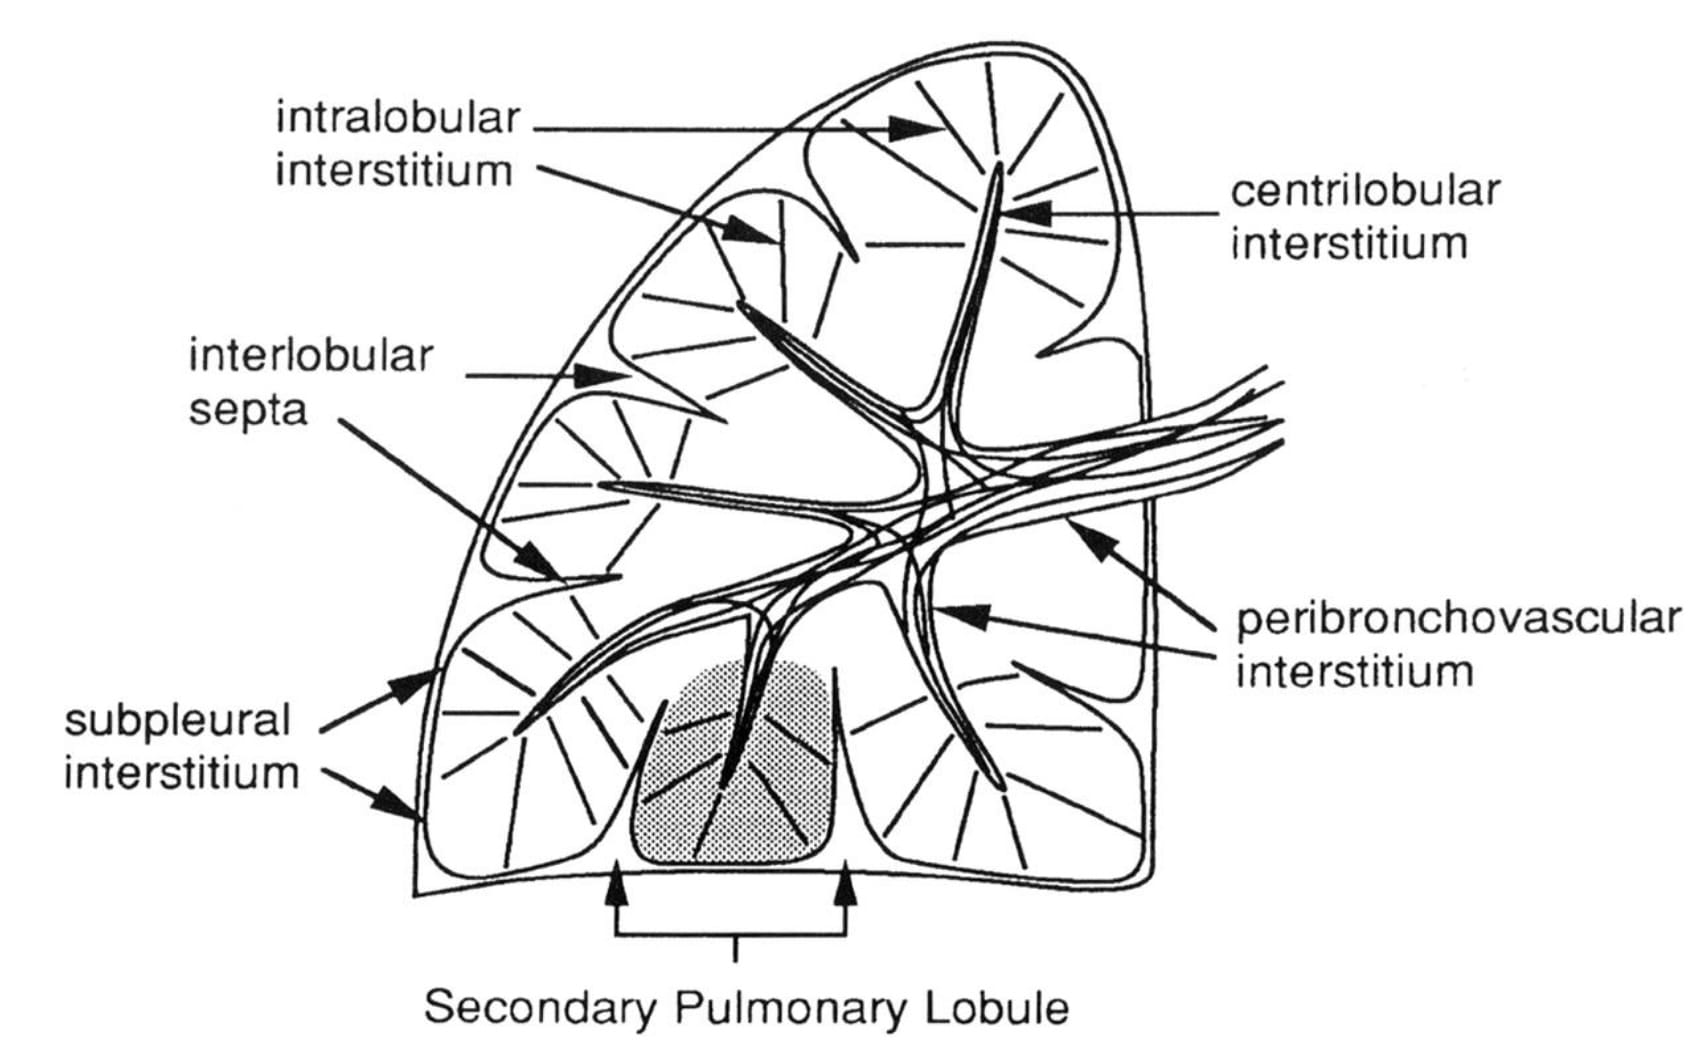

To understand this, we need to review the anatomic constituents of the pulmonary interstitium.

The axial connective tissue compartment is constituted by the bronchovascular sheaths surrounding broncho-arterial bundles and pulmonary veins. The parenchymal compartment is constituted by the alveolar septa (intralobular interstitium) and the peripheral, subpleural interstitium, anatomically continuous with interlobular septa.

When water accumulates in these locations, the corresponding imaging findings are, respectively:

- peribronchial fluid cuffs

- apparent thickening of the interlobar fissures

- septal lines

- Imaging findings of interstitial lung edema reflect the anatomic interstitial compartments of the lung: the axial, peri-bronchovascular; the sub-pleural; and the interlobular septal compartments